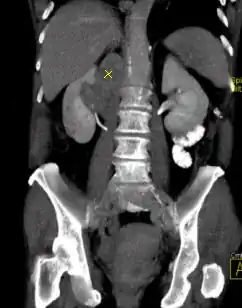

Die Schwächungseigenschaften von Geweben und Kontrastmittel sind von der Photonenenergie der verwendeten Röntgenstrahlung abhängig. Da im CT-Bild die Hounsfield-Werte von Kontrastmittel denen von Kalzifikationen ähneln, ist beispielsweise die Differenzierung zwischen Koronarkalk und Kontrastmittel im konventionellen CT-Bild bisweilen schwierig. Da Kontrastmittel im niederenergetischen Spektrum aber eine deutlich höhere Absorption als im höherenergetischen Spektralbereich zeigt, kann mit Hilfe der Multi-Energy-Computertomografie eine Differenzierung zwischen Kalk, bzw. Knochen und Kontrastmittel erfolgen. Knochen und Kalk können so einfach und zuverlässig aus dem Bild entfernt werden, wenn sie die Darstellung und Befundung anderer Bereiche behindern. Da sich mit der Zwei-Spektren-CT auch die Zusammensetzung des untersuchten Gewebes analysieren lässt, ist eine Charakterisierung von Nierensteinen hinsichtlich ihrer Zusammensetzung möglich. Mit dieser Technologie können auch Blutungen besser beurteilt und die Perfusion des Myokard dargestellt werden.[16]